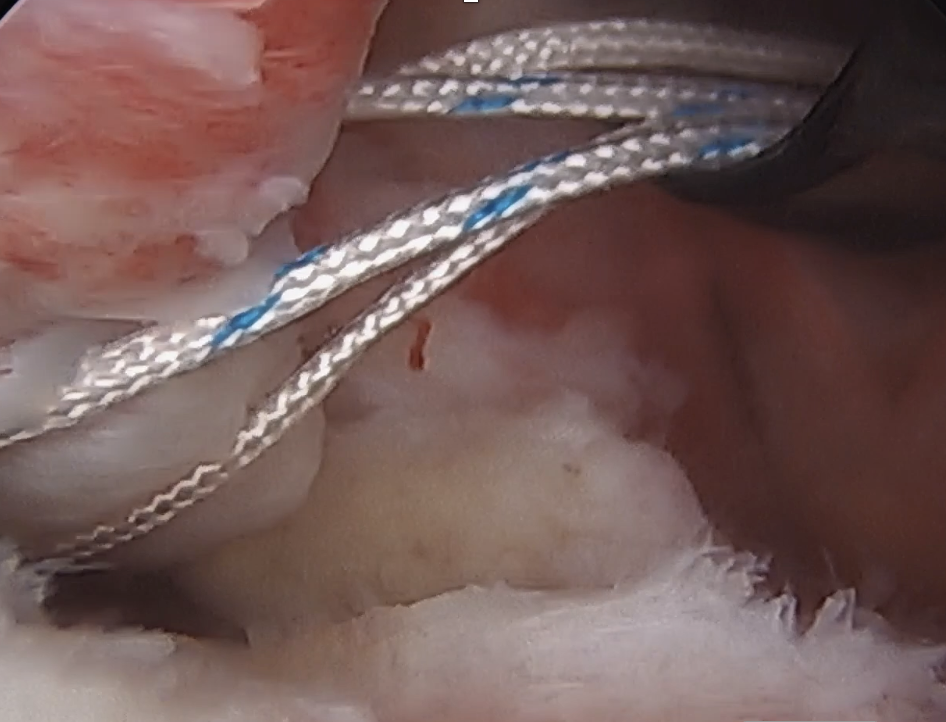

Anterolateral portal of Wilminton at anterolateral border of the acromion used to tag and release biceps

Insert anchor through anterior portal into subscapularis footprint

Suture passage through anterior portal or anterolateral portal and tie sutures through anterior portal